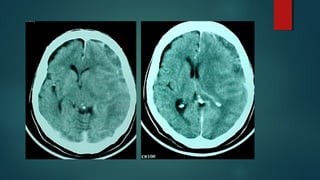

Este documento es el programa para un taller de imágenes del curso de emergencia 2015 impartido por el Dr. Víctor Delgado. El taller se centra en el uso de imágenes médicas para el diagnóstico y tratamiento de pacientes en coma traumático según la base de datos de Marshall. El Dr. Delgado es el único instructor repetido a lo largo del documento.